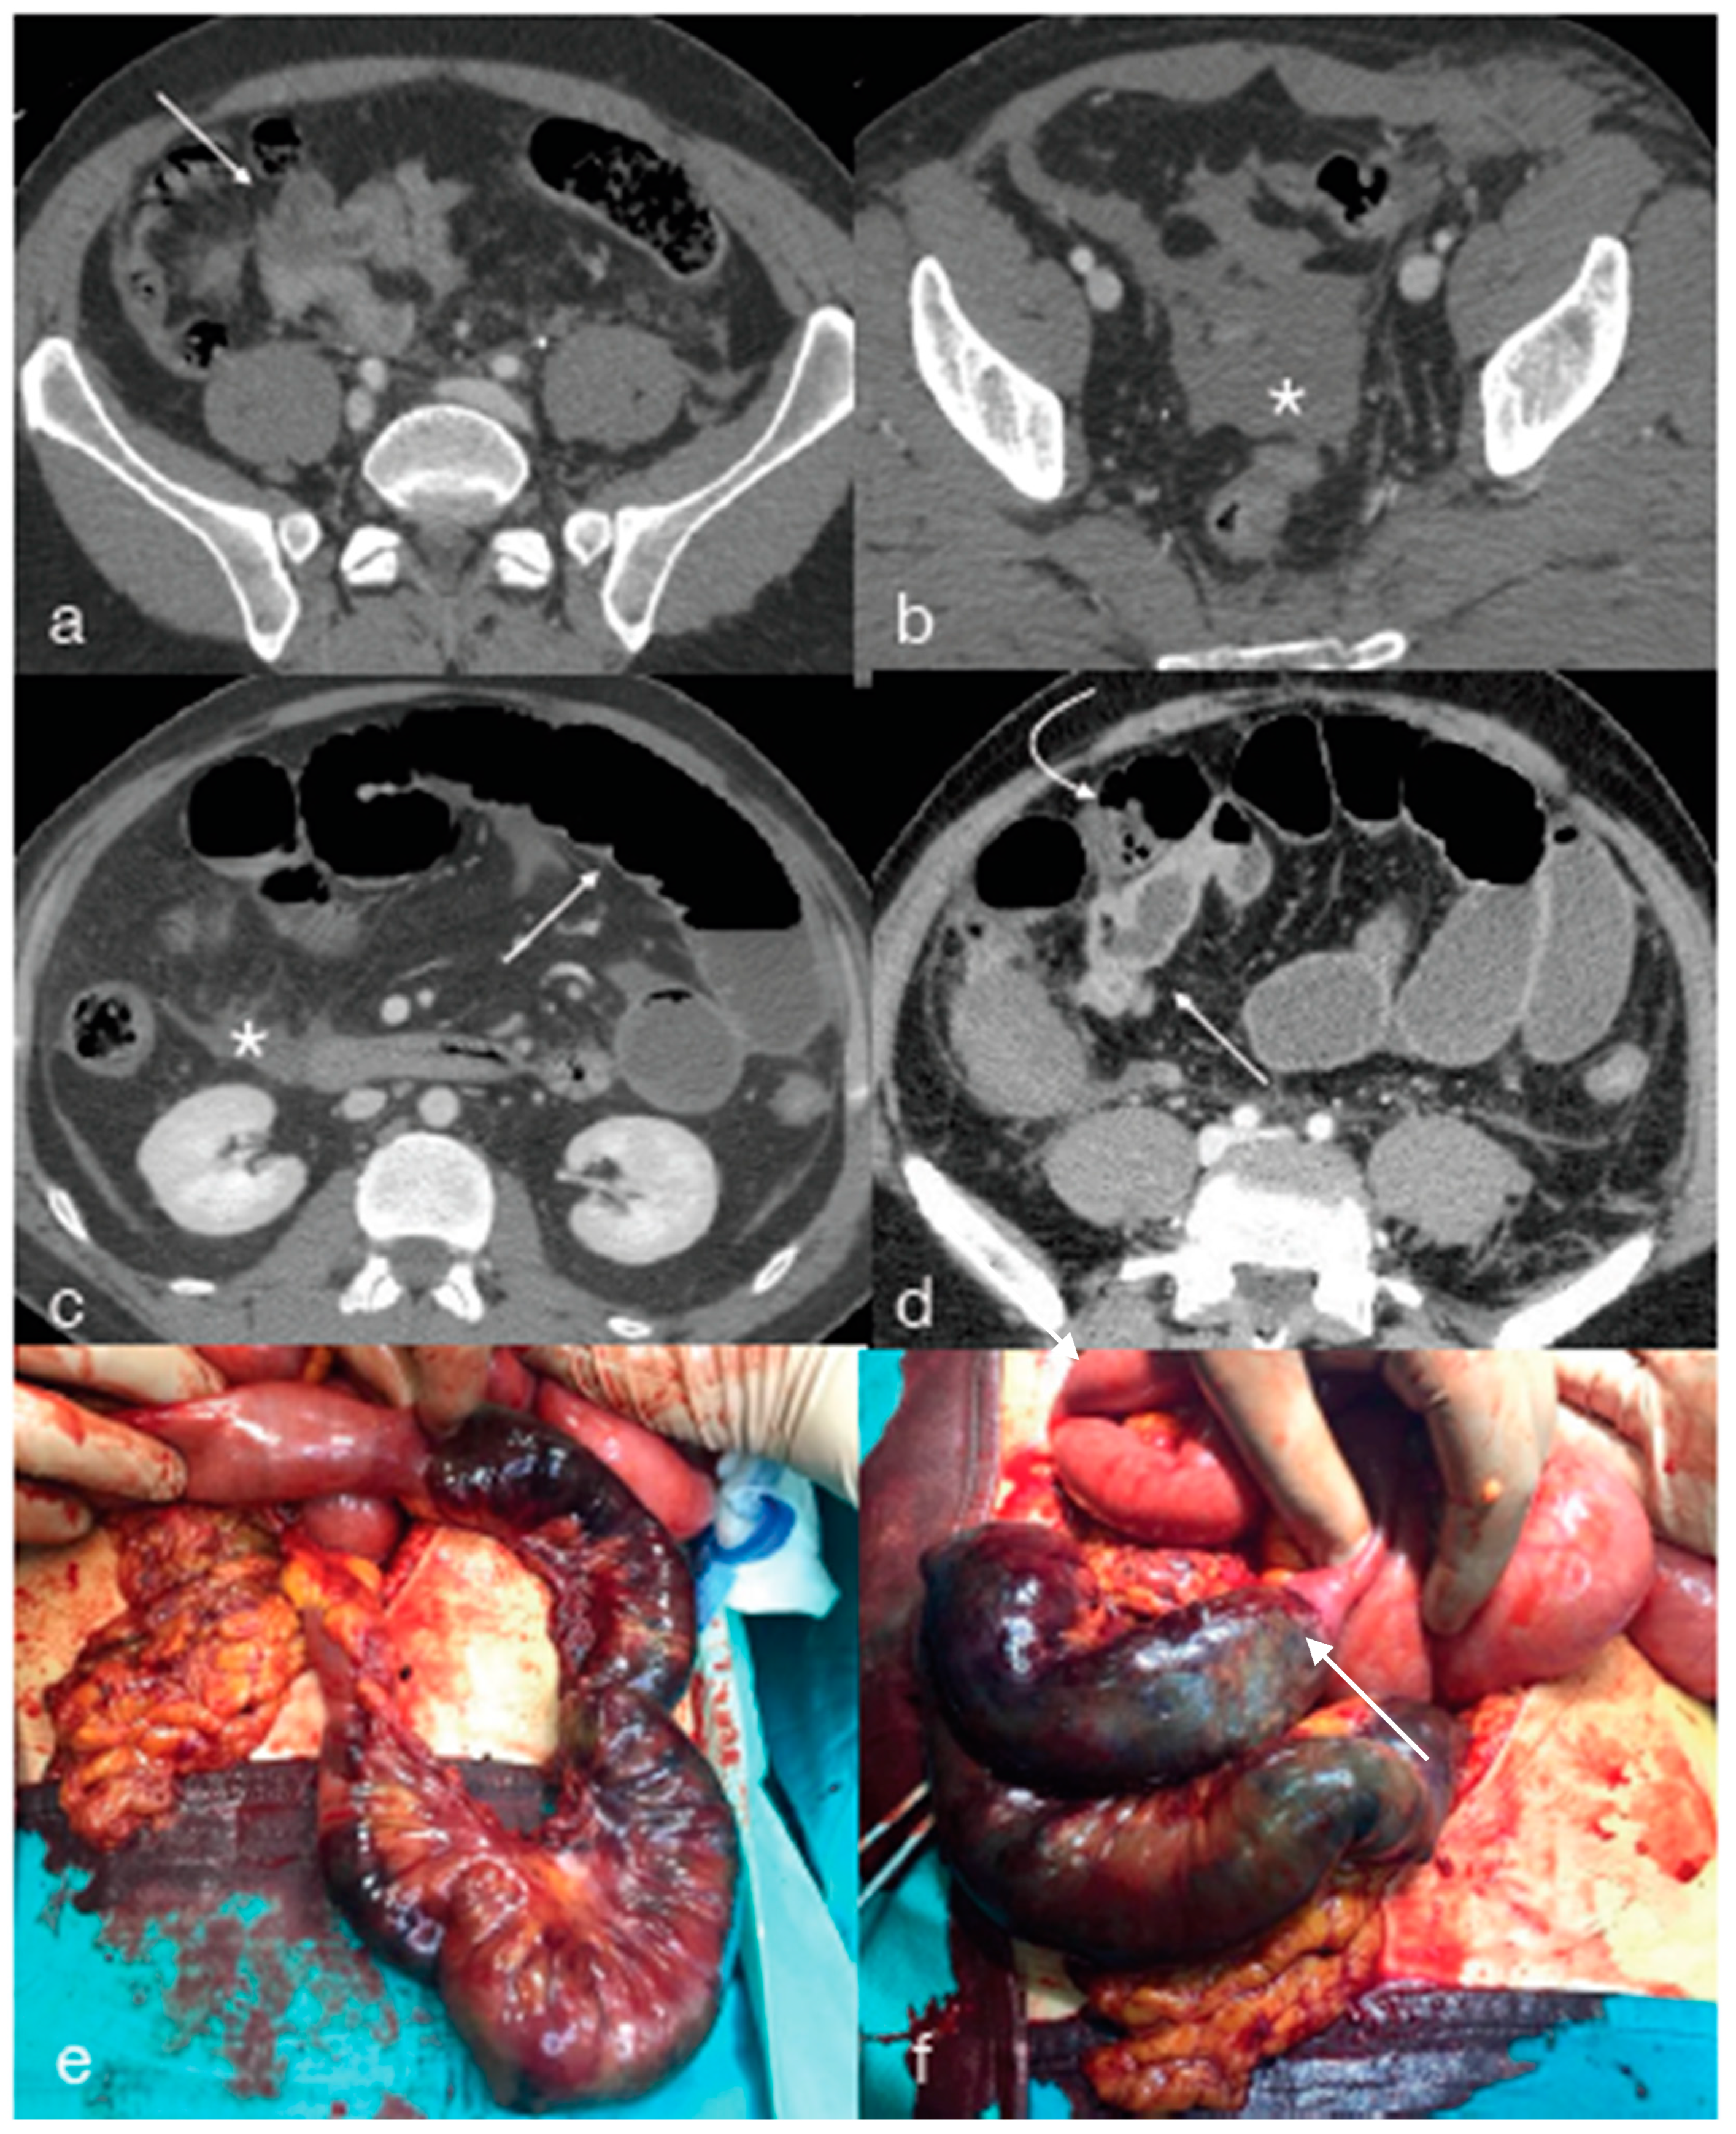

- Cinquantini, F.; Tugnoli, G.; Piccinini, A.; Coniglio, C.; Mannone, S.; Biscardi, A.; Gordini, G.; Di Saverio, S. Educational Review of Predictive Value and Findings of Computed Tomography Scan in Diagnosing Bowel and Mesenteric Injuries after Blunt Trauma: Correlation with Trauma Surgery Findings in 163 Patients. Can. Assoc. Radiol. J. 2017, 68, 276–285. [Google Scholar] [CrossRef] [PubMed]

- Smyth, L.; Bendinelli, C.; Lee, N.; Reeds, M.G.; Loh, E.J.; Amico, F.; Balogh, Z.J.; Di Saverio, S.; Weber, D.; Broek, R.P.T.; et al. WSES guidelines on blunt and penetrating bowel injury: Diagnosis, investigations, and treatment. World J. Emerg. Surg. 2022, 17, 1–15. [Google Scholar] [CrossRef] [PubMed]

- Raharimanantsoa, M.; Zingg, T.; Thiery, A.; Brigand, C.; Delhorme, J.-B.; Romain, B. Proposal of a new preliminary scoring tool for early identification of significant blunt bowel and mesenteric injuries in patients at risk after road traffic crashes. Eur. J. Trauma Emerg. Surg. 2017, 44, 779–785. [Google Scholar] [CrossRef]